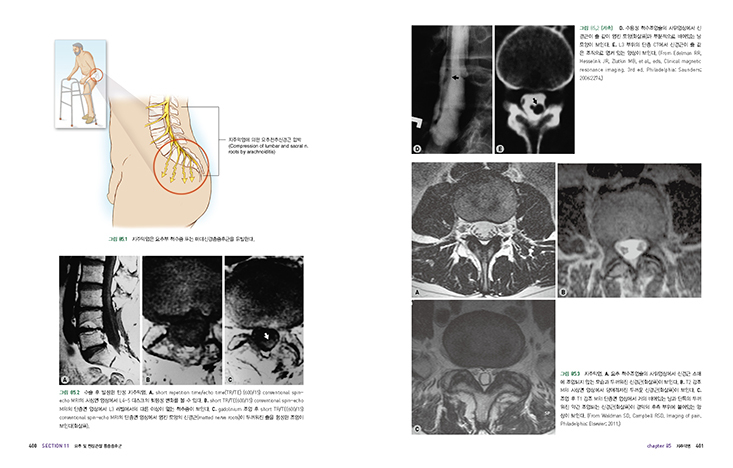

086 추간판염

087 천장관절통